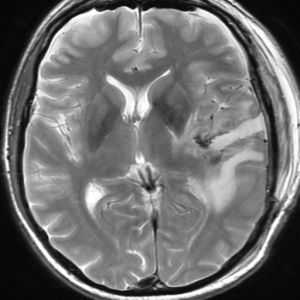

Решающими методами в диагностике субдуральной гематомы являются КТ и МРТ головного мозга. В диагностике острых гематом предпочтение отдается КТ головного мозга, которая в таких случаях выявляет однородную зону повышенной плотности, имеющую серповидную форму. С течением времени происходит разуплотнение гематомы и распад кровяных пигментов, в связи с чем через 1-6 нед. она перестает отличается по плотности от окружающих тканей. В подобной ситуации диагноз основывается на смещении латеральный отделов мозга в медиальном направлении и признаках сдавления бокового желудочка.

При проведении МРТ может наблюдаться пониженная контрастность зоны острой гематомы; хронические субдуральные гематомы, как правило, отличаются гиперинтенсивностью в Т2 режиме. В затруднительных случаях помогает МРТ с контрастированием. Интенсивное накопление контраста капсулой гематомы позволяет дифференцировать ее от арахноидальной кисты или субдуральной гигромы.

- КТ головного мозга - наиболее достоверный метод в остром периоде заболевания, позволяет на ранних стадиях выявить в проекции мозга гиперэхогенный участок серповидной формы. В случае хронической гематомы позволяет диагностировать признаки повышения внутричерепного давления и смещения мозговых структур.

- МРТ - варианты с введением контраста применяются в сомнительных ситуациях и в дифдиагностике с кистами и гигромами.